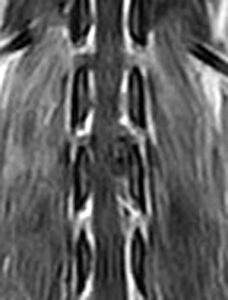

5~6歳以上の去勢手術をしていないオス犬に多い病気ですが、メス犬や去勢した犬に起こることもあります。お尻の筋肉が萎縮した結果、筋肉の隙間から直腸や膀胱が皮膚の下にとびでてしまいます。これにより便が出にくくなったり膀胱炎になったりします。手術をすることで機能回復および今後の致死的な状況を回避することができます。当院では去勢手術→結腸固定→前立腺固定→骨盤隔膜構成筋の縫縮→内閉鎖筋フラップ→浅臀筋フラップの順で通常腹側・臀部左右両側同時に行います。また老化以外に、筋肉が萎縮する原因があったり、腹圧がかかる原因があったりする場合も多いので、再発防止のためそれらの診断・治療も重要です。今回のワンちゃんも無事手術も終わり元気に退院しました。よかったね。